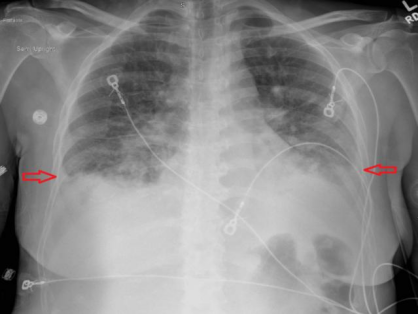

(1) 下肢B超:检查结果排除深静脉血栓形成(2)心电图:显示为窦性心律,存在 R 波递增不良(QTc 485ms)(图1),可排除急性冠脉综合征;(3)胸部 X 线(入院时):可见双侧斑片状阴影及双侧胸腔积液(图2);(4)病原学检查:入院时血培养、尿培养结果均为阴性,且住院期间无感染相关症状与体征,因此双侧斑片状阴影由感染因素导致的可能性较低,更倾向于与急性心力衰竭相关;(5)肺血管 CTA:因患者存在心悸、呼吸急促症状且 D - 二聚体水平轻度升高,遂完善此项检查以排除肺栓塞。结果显示双侧中量胸腔积液、轻度间质性肺水肿及轻度心脏肥大,提示存在充血性心力衰竭(CHF)(图 3、图 4),同时可见散在肺部阴影;(6)经胸超声心动图(TTE):显示左右心室大小正常、收缩功能正常,无局部壁运动异常;左心房大小为 2.93cm(正常范围 1.9-4.0cm),处于正常水平;肺动脉收缩压(PASP)为 34mmHg,存在轻度同心性左心室肥大,心室射血分数为 55%-60%。 (7)核素心肌灌注显像负荷试验:因心电图异常进行此项检查,未发现可逆性缺损,表明无心肌缺血;(8)腹部 / 盆腔 CT:患者肝炎免疫检测结果为阴性,肝转氨酶升高大概率由充血性心力衰竭(CHF)继发的充血性肝淤血引起。为进一步明确情况,行腹部 / 盆腔 CT 检查,显示存在胆结石、胆囊壁增厚 / 水肿、门静脉周围水肿所致的轻度肝肿大,同时伴有新出现的轻度全身性水肿及少量盆腔积液;(9)胸部 X 线(出院时):显示肺充血消退,双侧胸腔积液较入院时减少(图 5)。

图2